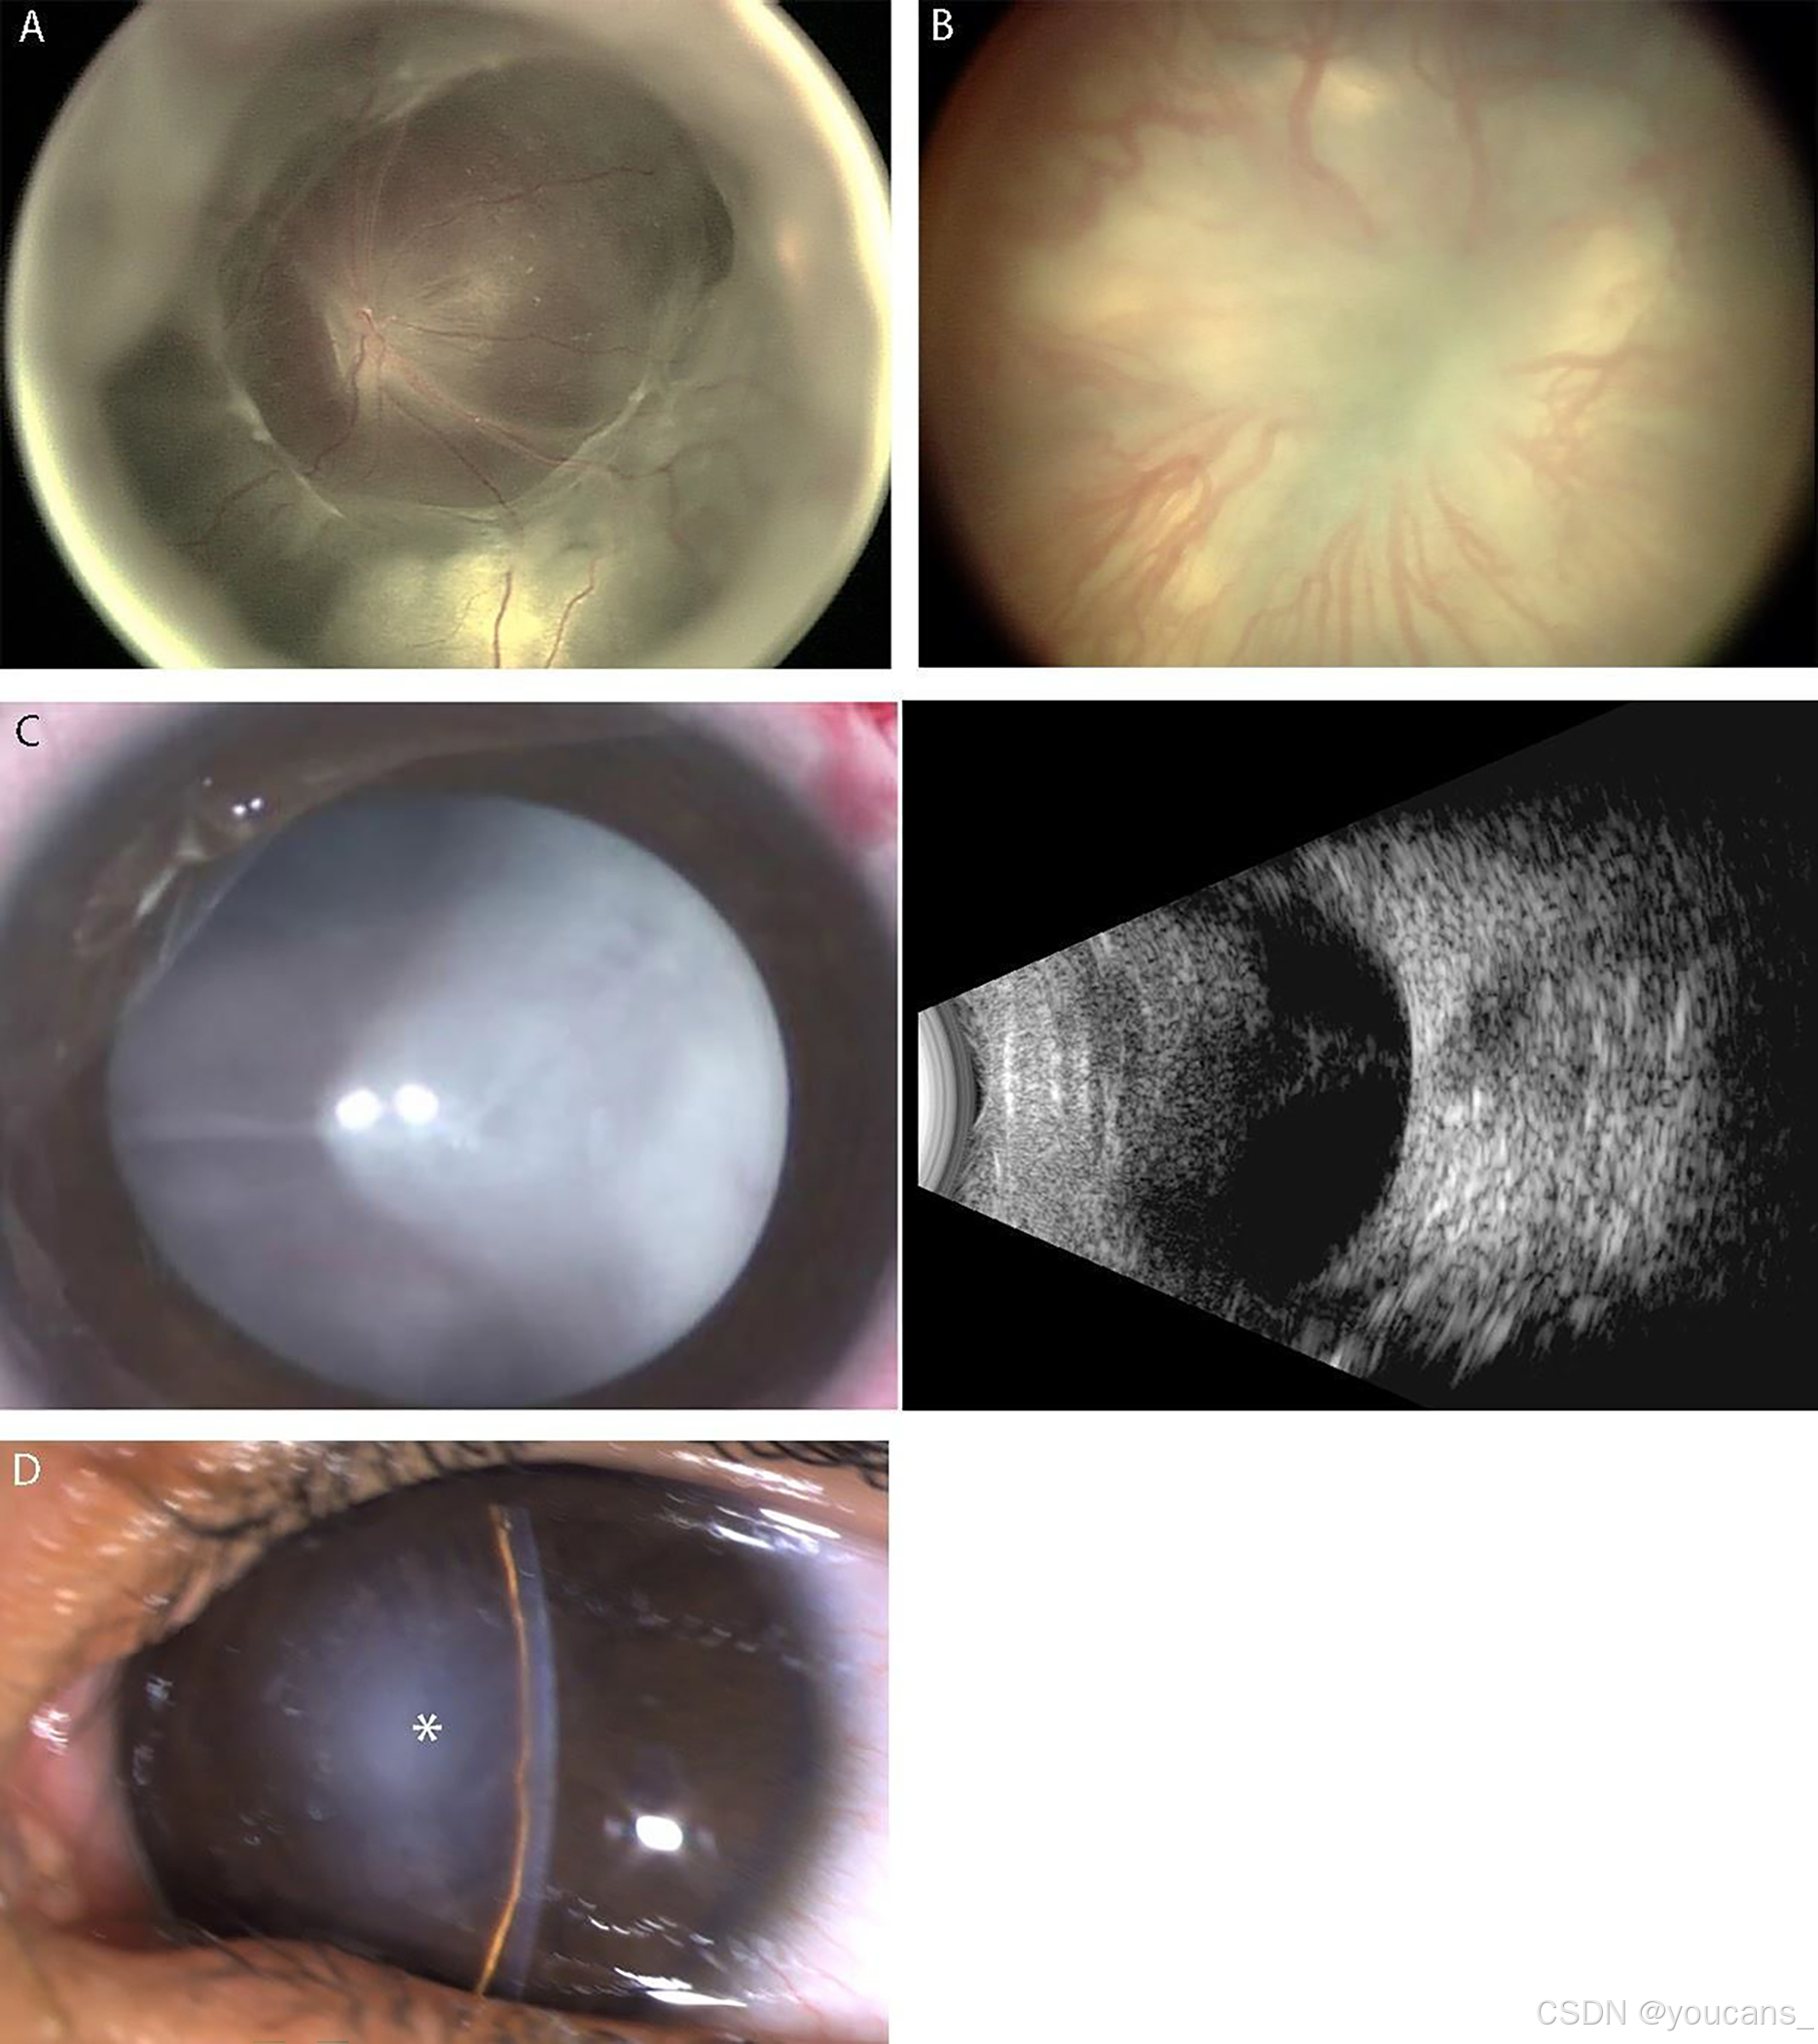

6.2 阶段5:完全视网膜脱落

完全视网膜脱落被定义为阶段5(见图10)。当纤维化阻碍了视网膜后极的可视化时,可以通过B扫描超声检查评估脱落的范围。委员会建议将完全脱落分为三种配置【30-32】:阶段5A,其中视神经盘可通过眼底镜观察到(见图10A,提示开放漏斗状脱落);阶段5B,其中视神经盘因视网膜后纤维血管组织或闭合漏斗状脱落而不可见(见图10B–C);阶段5C,其中阶段5B的表现伴随前节异常(例如,晶状体前移、前房明显变浅、虹膜晶状体粘连和/或晶状体-内皮粘连伴中心角膜混浊)(见图10D,提示闭合漏斗配置)【4,33】。

如果临床上有用,可以应用漏斗配置的其他描述符(例如开闭式)。

图10. 展示早产儿视网膜病(ROP)阶段5的例子。

A. 宽角眼底照片显示阶段5A ROP,特征为视网膜完全脱落且视神经盘可见。注意开放漏斗状配置。

B. 宽角眼底照片显示阶段5B ROP,视神经盘无法看到,因视网膜后纤维血管组织的遮挡。

C. 阶段5B ROP的前节正常外观照片(左侧),因视网膜后纤维血管组织的遮挡无法看到视神经盘或视网膜。B扫描超声检查(右侧)显示完全视网膜脱落,并呈后部闭合漏斗状配置。

D. 外部照片显示阶段5C ROP的前节特征,伴有前晶状体移位、前房明显变浅、中央虹膜晶状体内皮粘连和中央角膜混浊(星号),这些都阻止了对闭合漏斗状视网膜脱落的观察。

图10B:已获得Arch Ophthalmol 2005;123:991-999的图像使用授权。